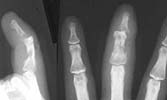

Presenting this case for opinion on management. 34 year old cottage industrialist not able to attend to work following a human bite on his left middle finger one month ago. Patient has received treatment elsewhere where incision, drainage of pus and debridement of sloughed tendons were done along with antibiotics based on culture and sensitivity. At present wounds on the dorsal and volar aspect of middle segment with absent tendons, exposed bones and unstable DIP joint. Infection still present. Stiffness PIP joint present. Clinical picture and xrays attached.

I have advised a ray amputation. Who will vote with me? Any other plans to reduce morbidity and early functional return?